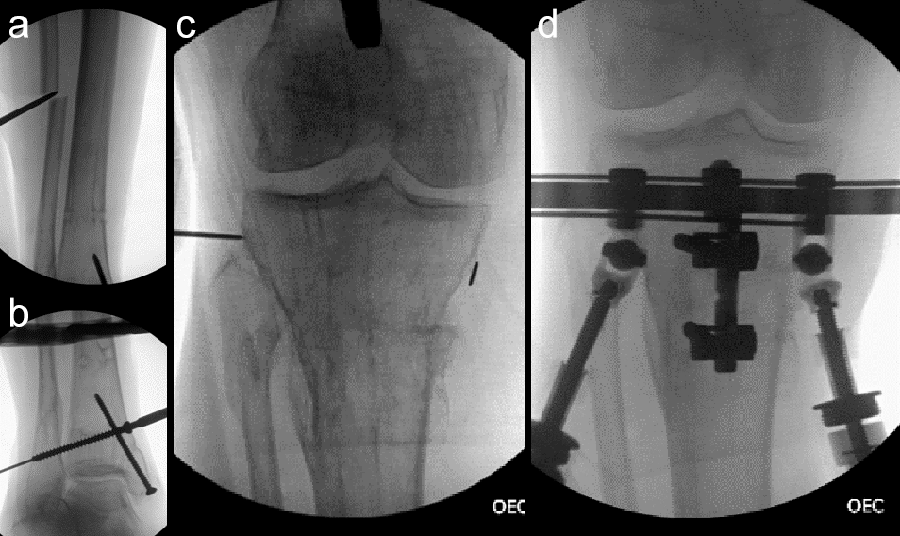

- 47-year-old woman s/p separate femur and tibia trauma

- Valgus knee with external rotation through femur

- Deformity analysis revealed that the angular deformity was coming from her proximal tibia.

The treatment plan was to remove the femoral intramedullary (IM) nail, to perform a derotational osteotomy of the femur with an internal saw, and then to refix the femur with a new antegrade IM nail.

The tibial deformity was planned to be managed with a MAXFRAME AUTOSTRUT™.